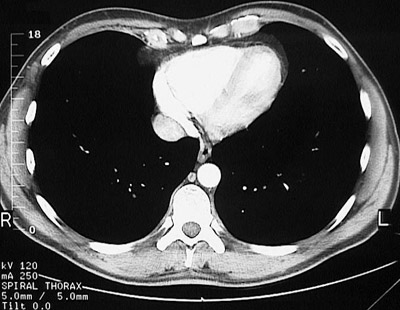

[T10] This is a normal chest CT scan demonstrating the right lung and left lung and inferior vena cava and right atrium and right ventricle and interventricular septum and left ventricle and xyphoid process and descending aorta and azygous vein and esophagus and serratus anterior muscle and latissimus dorsi muscle and trapezius muscle and sacrospinalis muscle and transversospinal muscle in the upper chest.